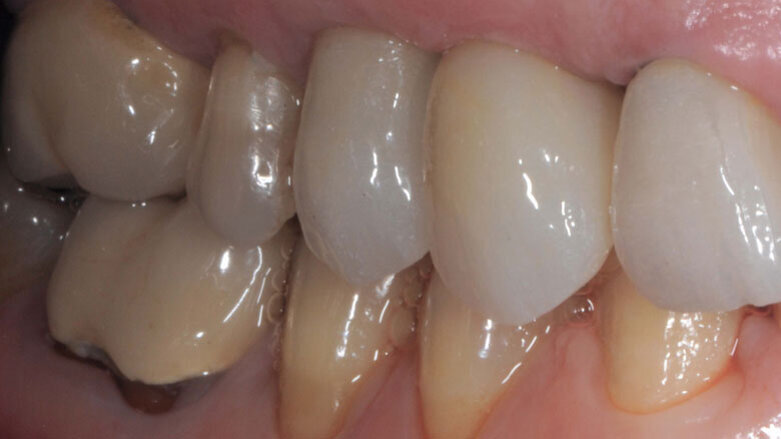

Le corone sui denti 1.3 e 1.4 furono rimosse, il dente 1.3 fu estratto e l’alveolo fu riempito con una membrana di PRGF ottenuta tramite centrifugazione del sangue della paziente con il sistema Endoret e un provvisorio fu consegnato sui denti 1.3 e 1.4 (Fig. 5, 6). Dopo otto settimane fu eseguita una nuova cone-beam e la chirurgia fu pianificata (Fig. 7). Si eseguì un lembo a tutto spessore, fu eseguita l’osteotomia e fu inserito un impianto BTI Core 3.5 × 8.5. Un pilastro Unit fu avvitato e un tappo di guarigione fu applicato. L’osso ottenuto dalla fresatura mescolato con una membrana di PRGF fu applicato sul lato palatale per compensare una piccola deiscenza, una seconda membrana fu applicata sopra l’osso circostante e un innesto di tessuto connettivo prelevato dalla tuberosità fu suturato vestibolarmente per ricreare la bozza canina. Punti di sutura staccati furono eseguiti con un filo in PTFE (Figg. 8-11). Dopo quattro mesi il provvisorio fu rimosso e i tessuti apparivano sani e con un buon spessore di tessuto connettivo vestibolare per garantire la stabilità nel tempo del risultato. Fu eseguita un’impronta con la tecnica del cucchiaio aperto e dopo due settimane furono consegnate una corona in zirconio cementata sul dente 14 ed una avvitata sul denta 1.3. Il profilo di emergenza della corona sull’impianto appariva ideale. Purtroppo, a causa della mancanza del picco osseo sul versante distale del dente 1.2, non si ottenne una papilla di altezza adeguata. Ciononostante la paziente si disse soddisfatta del risultato e rifiutò ulteriori terapie per correggere il difetto residuo (Figg. 12-15).

La presenza di difetti ossei dopo l’apicectomia eseguita sul dente 1.2 fece decidere di non eseguire un impianto post-estrattivo immediato. La presenza dei difetti ossei e la presenza di cicatrici a carico dei tessuti molli rendeva di difficile esecuzione procedure di GBR che richiedessero il rilascio dei lembi. Si decise pertanto di compensare la perdita di tessuto vestibolare con un innesto di tessuto connettivo. L’inserimento di un impianto di 8,5 mm permise di ottenere un asse di inserzione ideale e di avere il foro di fuoriuscita della vite collocato palatalmente senza il bisogno di correggere l’angolazione. Tutto ci. ha permesso di eseguire procedure chirurgiche e protesiche semplici e ben sopportate dalla paziente e soprattutto di raggiungere un buon risultato estetico e funzionale.